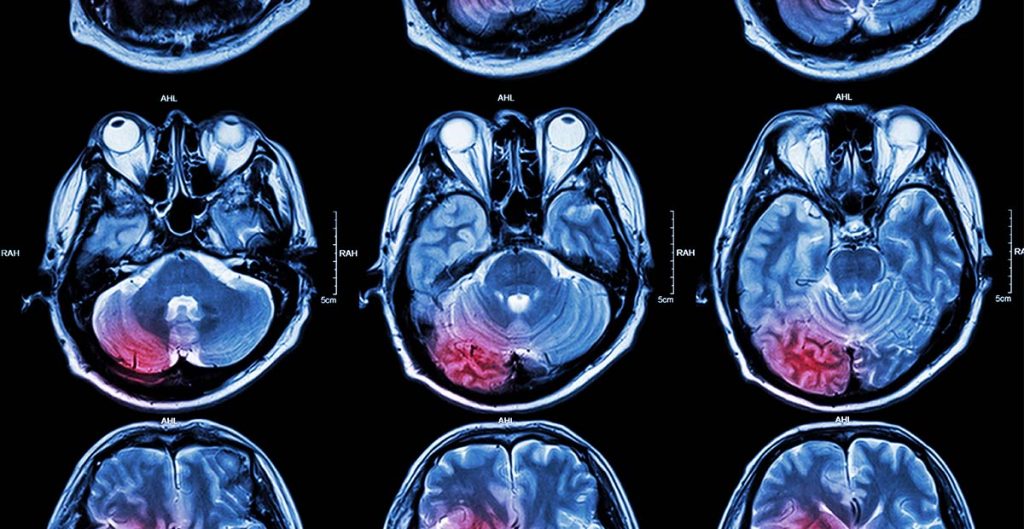

• Efectuarea de imagistica medicala – cea mai concludenta in acest sens este o investigatie  RMN cerebral, care sustine suspiciunea diagnosticului;